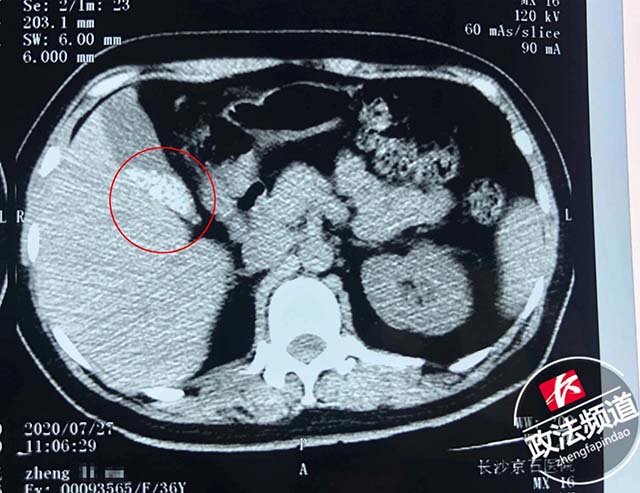

患者术前CT,红圈内白色部分为胆囊结石

7月28日医生为郑女士施行了经脐无痕保胆取石术,成功保留了患者功能尚存的胆囊、并取出百颗直径约5mm左右的胆囊结石。